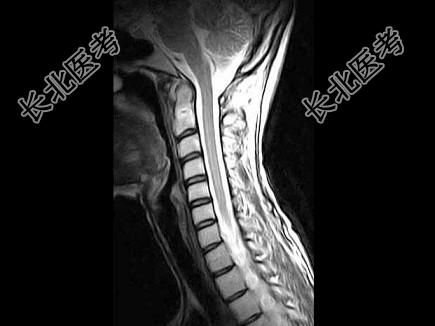

- 单项选择题女,29岁, 有午后发热,夜间盗汗, 消瘦等,枕颈部疼痛, 活动头部时加重,休息后减轻, 结合所提供的图像,最可能的诊断是 ( )

D、寰枢椎结核